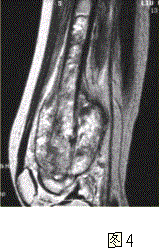

问题 患者男,16岁,左大腿下部疼痛伴肿胀2个月,逐渐加重。自感左膝上方胀痛,尤以夜间为著,伴行走困难。既往史及家族史无特殊。查体:左大腿下部明显肿胀,皮温较对侧升高。碱性磷酸酶明显增高。股骨平片及MRI见下图。 你认为对定性诊断有价值的征象是

选项 A.病变边缘模糊,内部信号不均 B.病变边缘骨皮质完整 C.病变周围可见软组织肿块 D.病变边缘可见骨膜反应,Codman三角形成 E.MR示病变周围骨髓明显水肿 F.病变内未见钙化影

答案 ACDEF